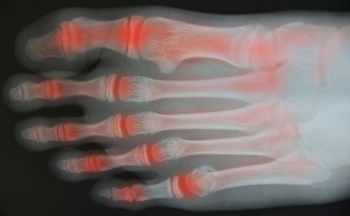

Rheumatoid arthritis, which is referred to as RA, is an extremely painful and often debilitating disease that causes inflammation in joints. It can occur in the feet and ankles, often affecting the small interphalangeal joints in the toes first. RA may also develop in the metatarsophalangeal joint in the big toe, as well as the subtalar joint that connects the ankle with the foot. RA can damage other structures in the feet and ankles, and may lead to the formation of nodules in ligaments and tendons. Additionally, corns and calluses may form on the skin. Damage from RA may change the shape of affected joints and cause the toes to become twisted and deformed, as in hammertoes and bunions. RA flares can affect people differently. Symptoms from an RA flare can last for days, weeks, or even months and it may be difficult to walk. Professional care from a podiatrist can help ease symptoms, improve mobility, and help to lessen future damage to affected joints.

Rheumatoid Arthritis (RA) is an autoimmune disorder in which the body’s own immune system attacks the membranes surrounding the joints. Inflammation of the lining and eventually the destruction of the joint’s cartilage and bone occur, causing severe pain and immobility.

Rheumatoid Arthritis of the Feet

Although RA usually attacks multiple bones and joints throughout the entire body, almost 90 percent of cases result in pain in the foot or ankle area.